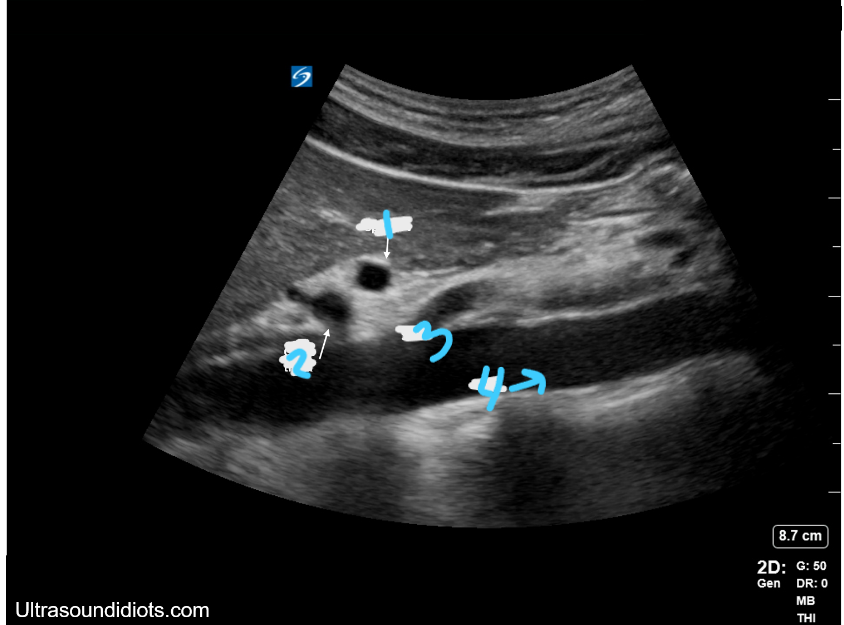

<p>In this Sagittal view, what is #1?</p>

In this Sagittal view, what is #1?

<p>In this Sagittal view, what is #2?</p>

In this Sagittal view, what is #2?

<p>In this Sagittal view, what is #3?</p>

In this Sagittal view, what is #3?

<p>In this sagittal plane, what is #1?</p>

In this sagittal plane, what is #1?

<p>In this sagittal plane, what is #2?</p>

In this sagittal plane, what is #2?

<p>In this sagittal plane, what is #3?</p>

In this sagittal plane, what is #3?